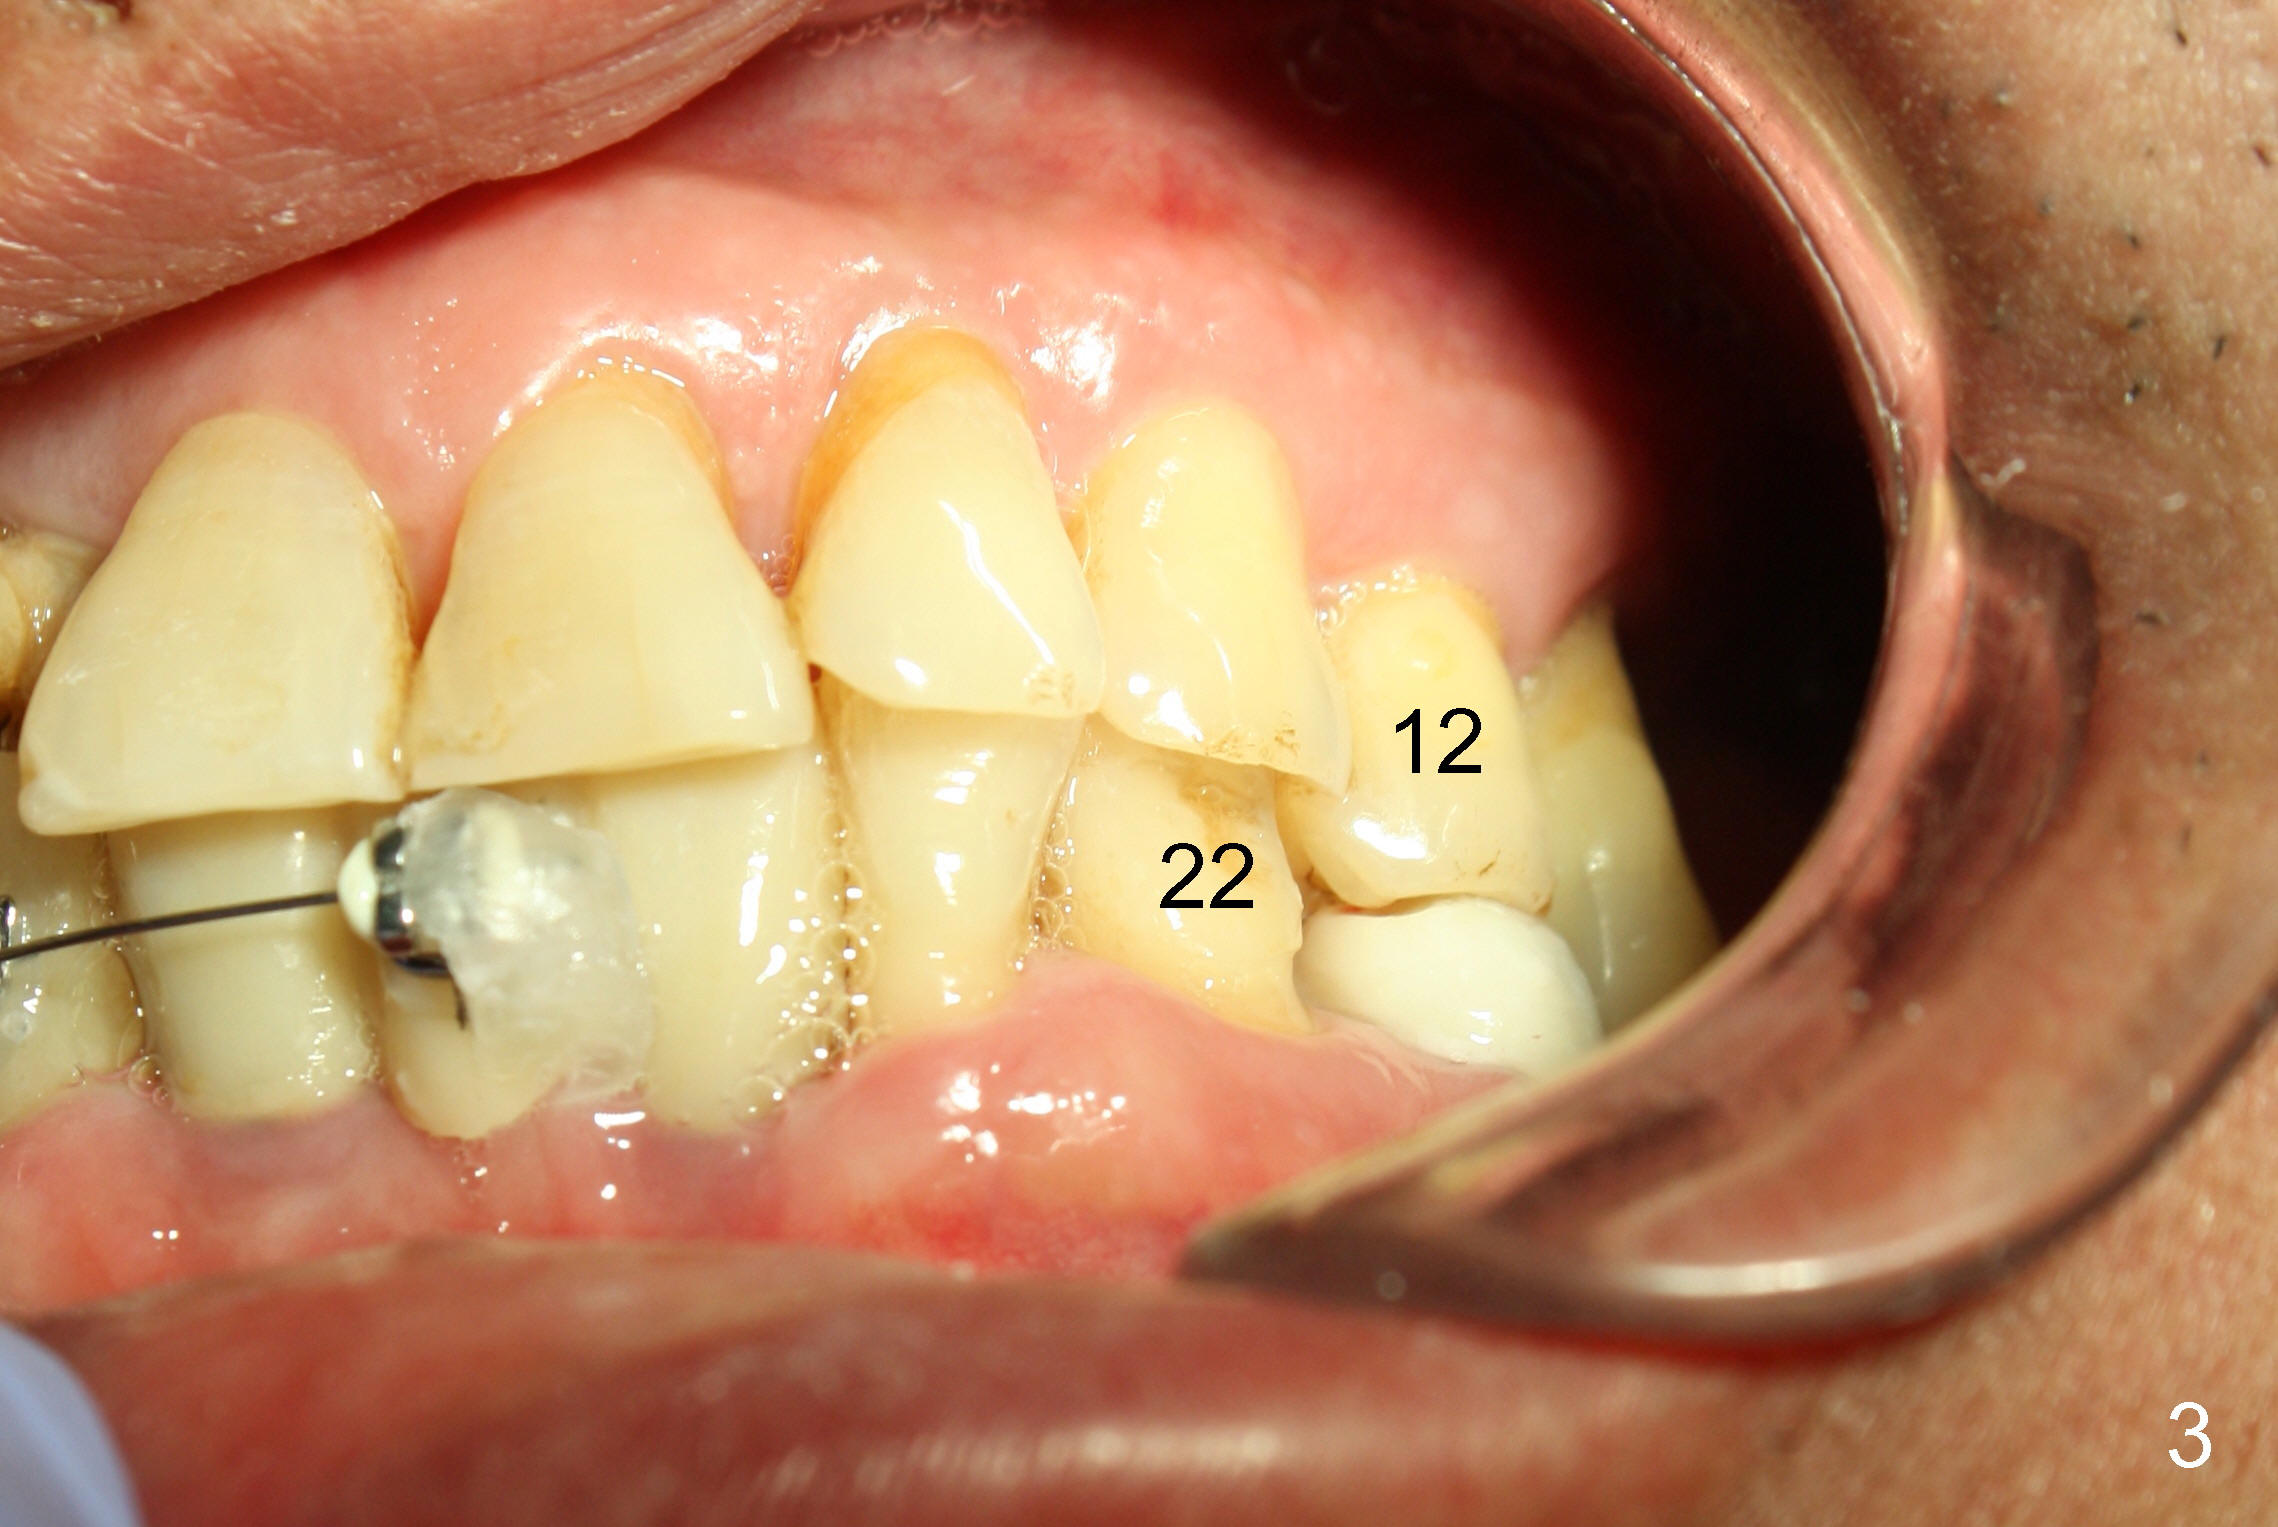

The main purpose of the 1st stage of ortho is to intrude the tooth #29 using implants at the sites of #28,30 as anchorages (Fig.1,2). If possible, intrusion of #27 is also needed. Since #24-26 is an implant supported bridge, one bracket in the pontic appears to be sufficient (Fig.2). Bracketing is also planned to extend to the lower left until #21 to distalize #22 (Fig.3). Supraeruption of #12 blocks the distalization. It appears that the supraeruption should be corrected after #13 implant placement (using the latter as an anchorage).